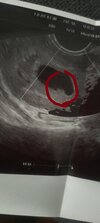

Byłam jeszcze u mojego lekarza prowadzącego. Miałam u niego monitoring więc wiemy że owulacja była wcześniej, dlatego nie wygląda to dobrze